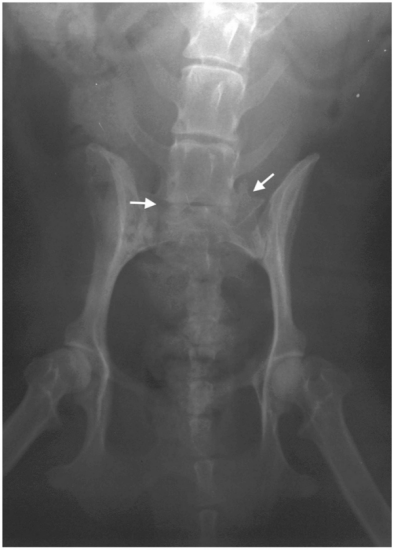

这只雌性混种犬就诊时情况令人揪心:后肢软弱无力,走路时膝盖弯曲变形,连最基本的爬楼梯都成了奢望,还出现了尿失禁症状。检查显示,它除了患有DLSS外,还伴有双膝骨关节炎。触诊时,腰骶部的疼痛反应明显,膀胱肿大,尾部张力减弱,种种迹象都表明病情已相当严重。

3. 精准注射将3000多万个细胞注入腰椎病变部位,同时在其膝关节内注入1500多万个细胞